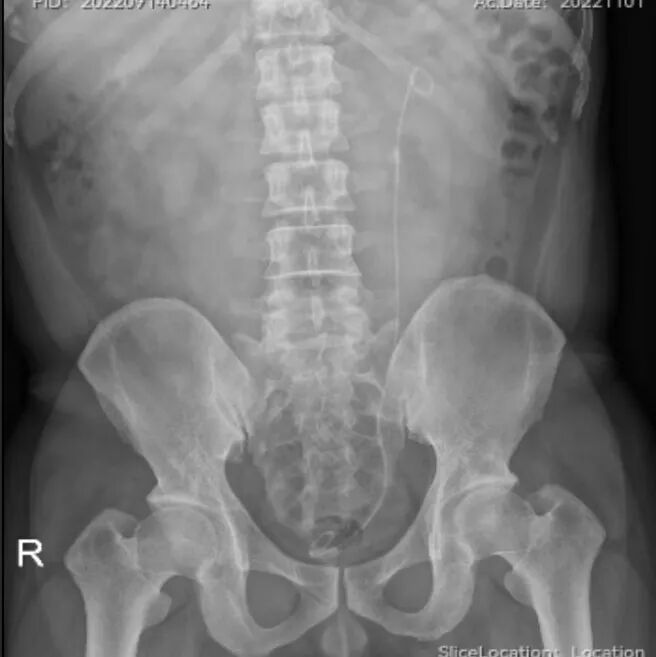

猪输尿管怎么吃泌尿外科医生常说的“猪尾巴管”是什么?_https://www.jmylbn.com_新闻资讯_第3张

结石术后留置的双J管